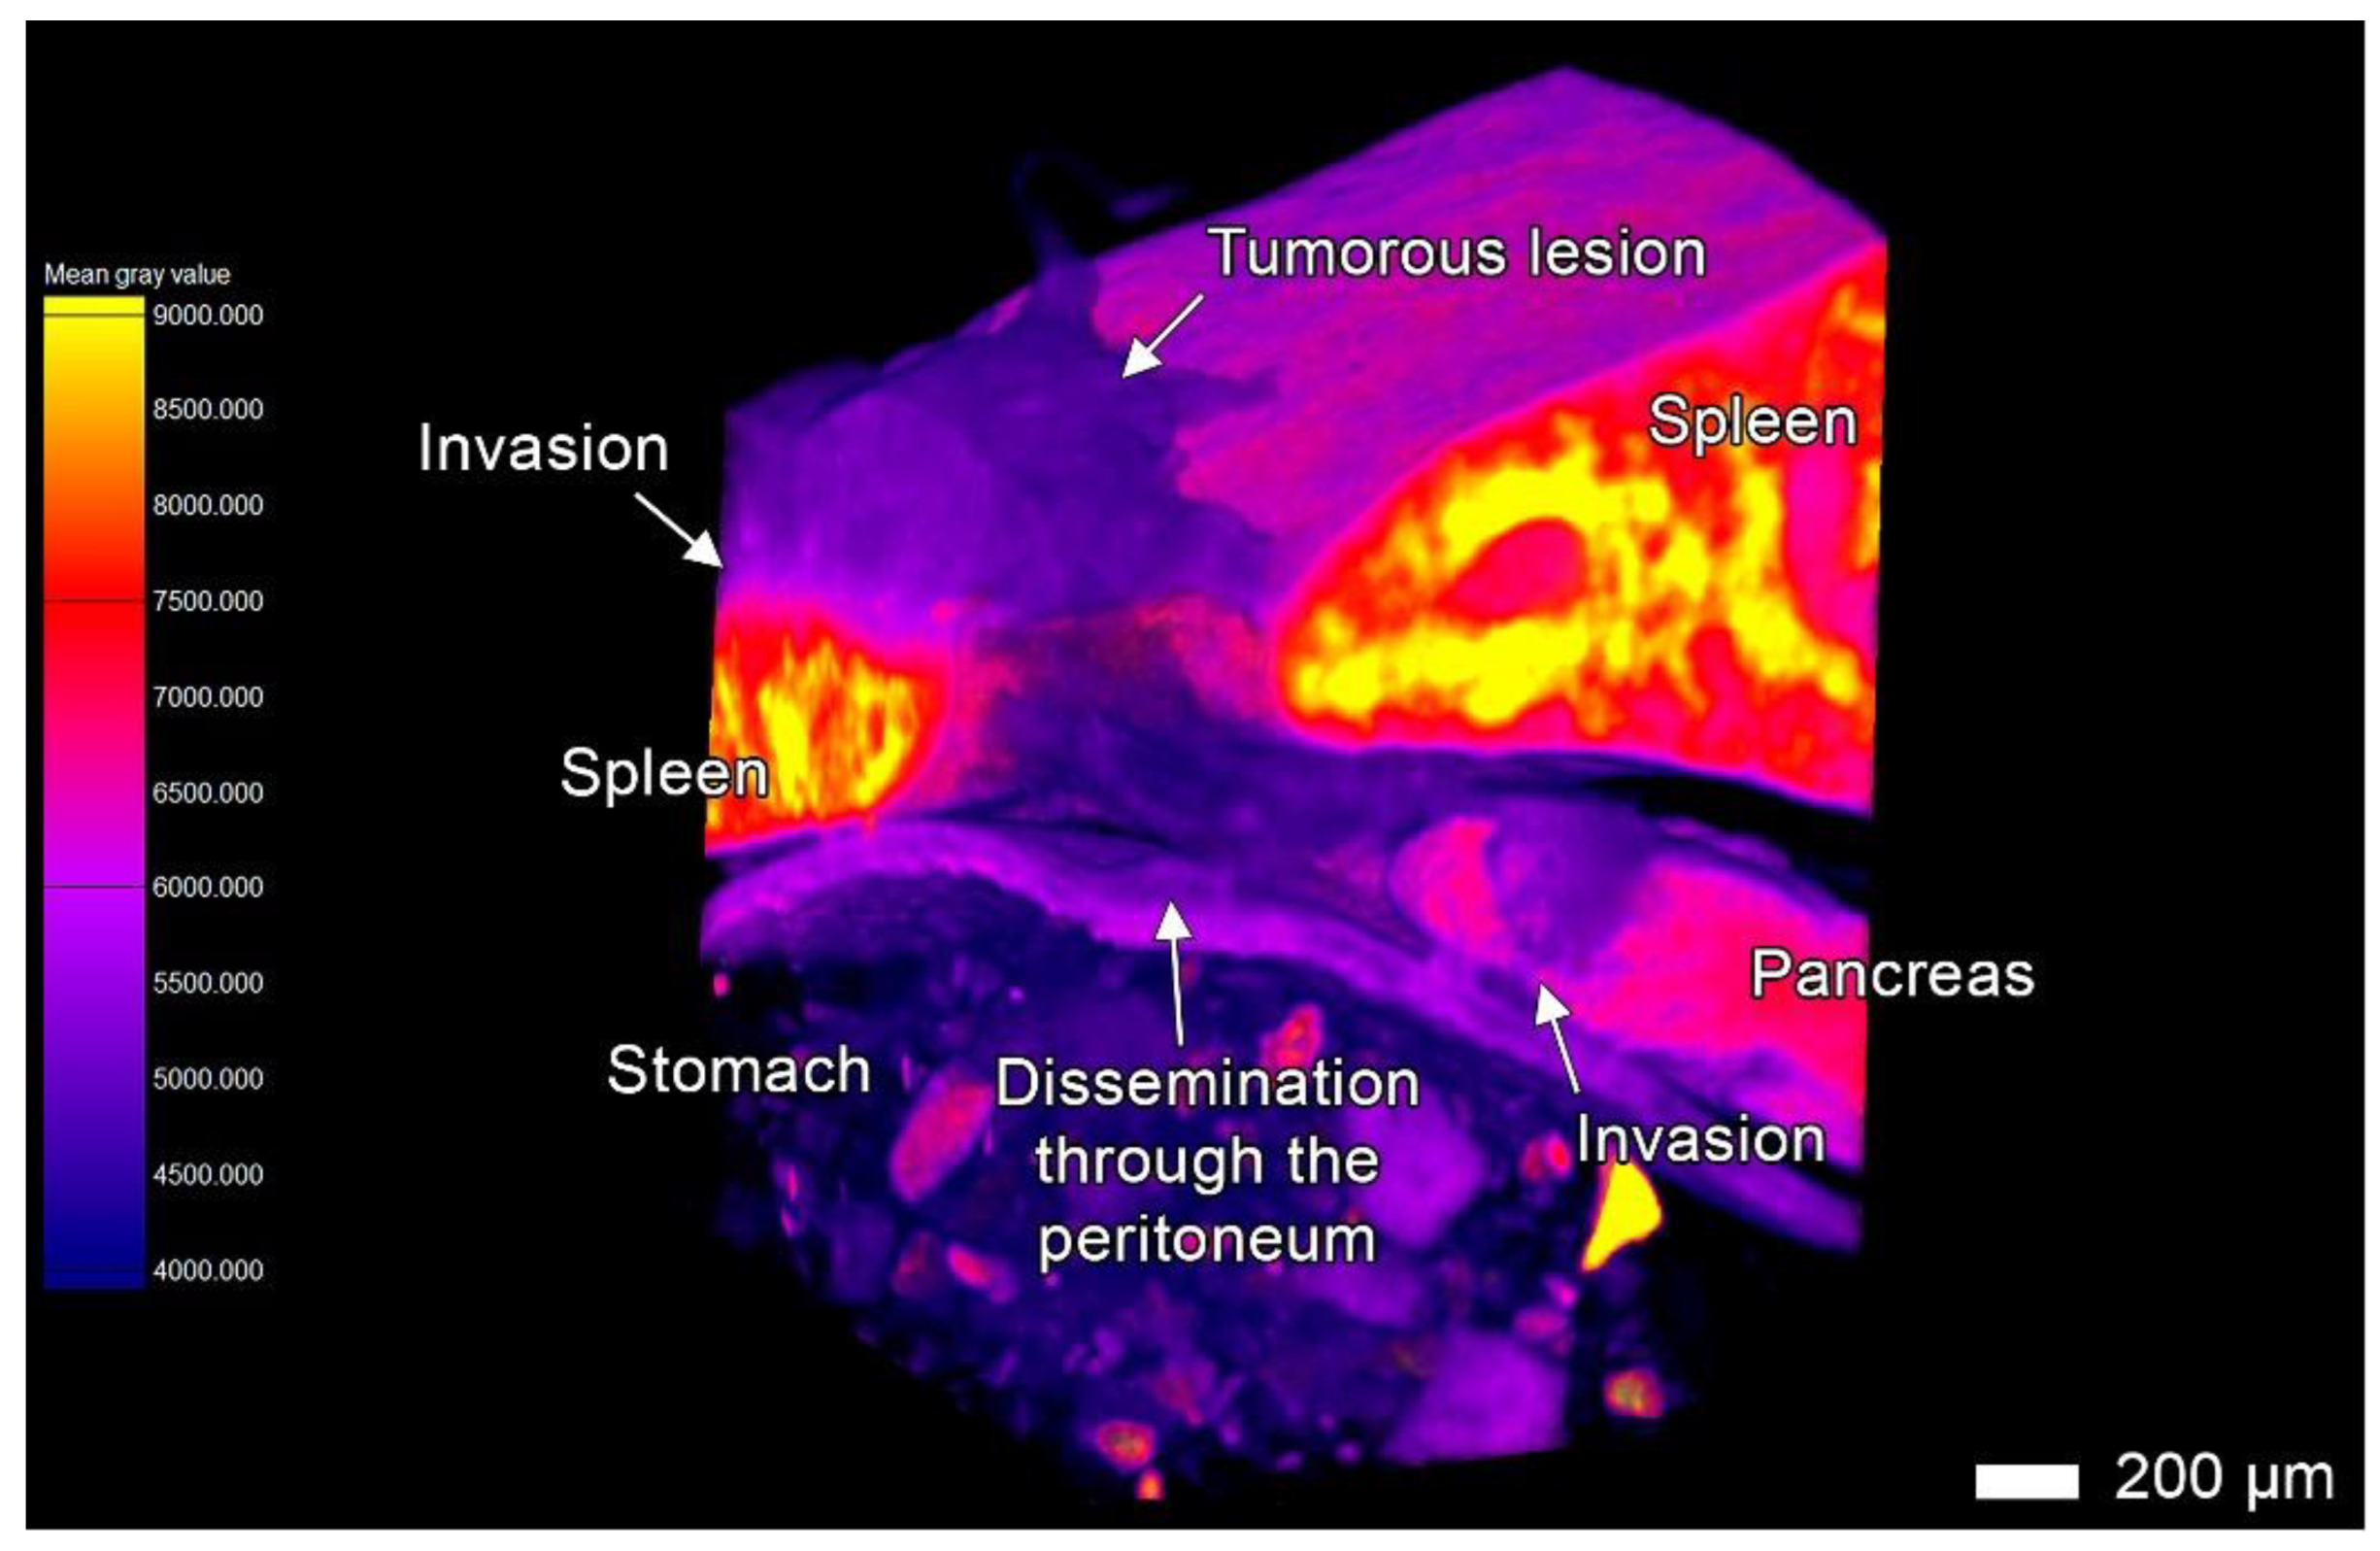

3.4. Tumor Invasion into the Pancreas

3.6. Peritoneal Dissemination